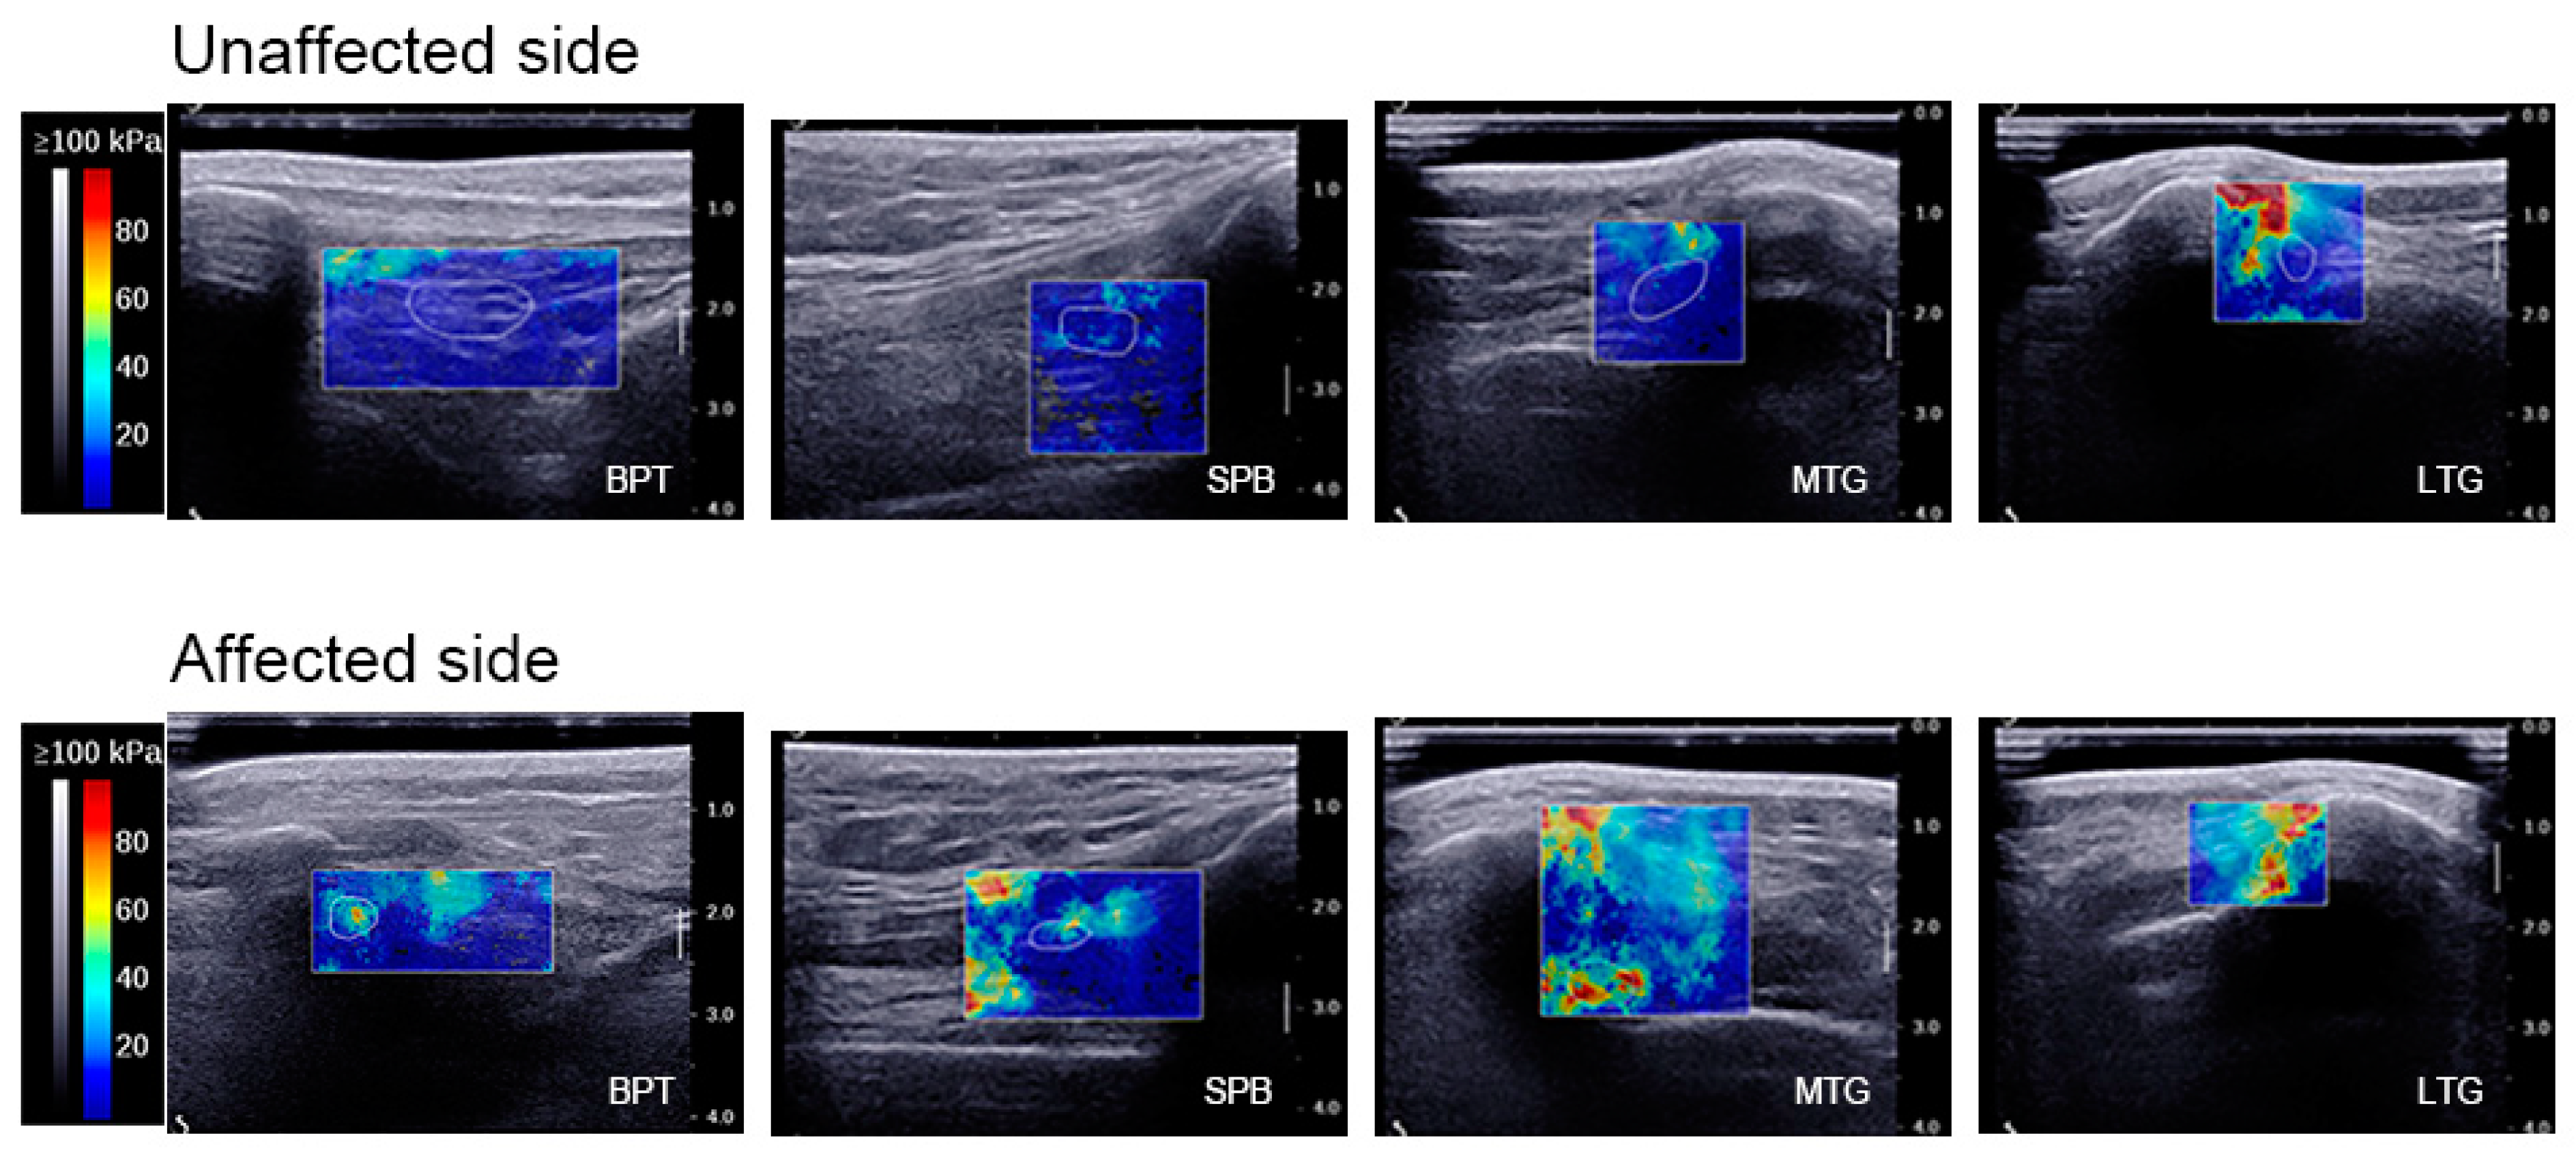

Figure 2.

Elastographic imaging. Elastographic imaging at 0° knee flexion: analysis of BPT, the SPB, the MTG, and the LTG on the unaffected side and affected side. The scar tissue was delineated by a white line (i.e., ROI) on the affected side, whereas the corresponding anatomical region was outlined on the unaffected side. Within the ROI, the colour map showed the relative SWE at each location in order of increasing value: blue, green, yellow, and red. BPT, below the patellar tendon; SPB, suprapatellar bursa; MTG, medial trochlear groove; LTG, lateral trochlear groove; ROI, region of interest.